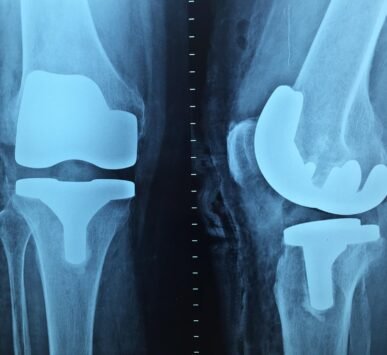

Dr. Reddy has received advanced training in arthroplasty and arthroscopy from leading medical centers in Germany, Singapore, and Australia. He is well known for his expertise in robotic joint replacement surgery, having performed more than 750 robotic-assisted procedures with excellent patient outcomes.